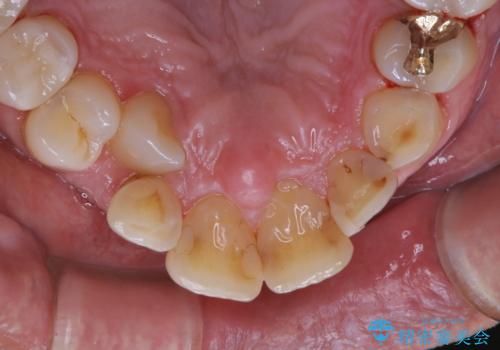

- 被せ物の治療が終了したためメンテナンスに入る前に全体的なチェック・クリーニングを行いました。

歯科衛生士による専門的なクリーニングPMTC(保険外治療)60分コースを行いました。

専門的な機械・材料を使用して徹底的に汚れを取り除きました。

染め出しをして、磨き残しの確認・ブラッシング指導も行いました。